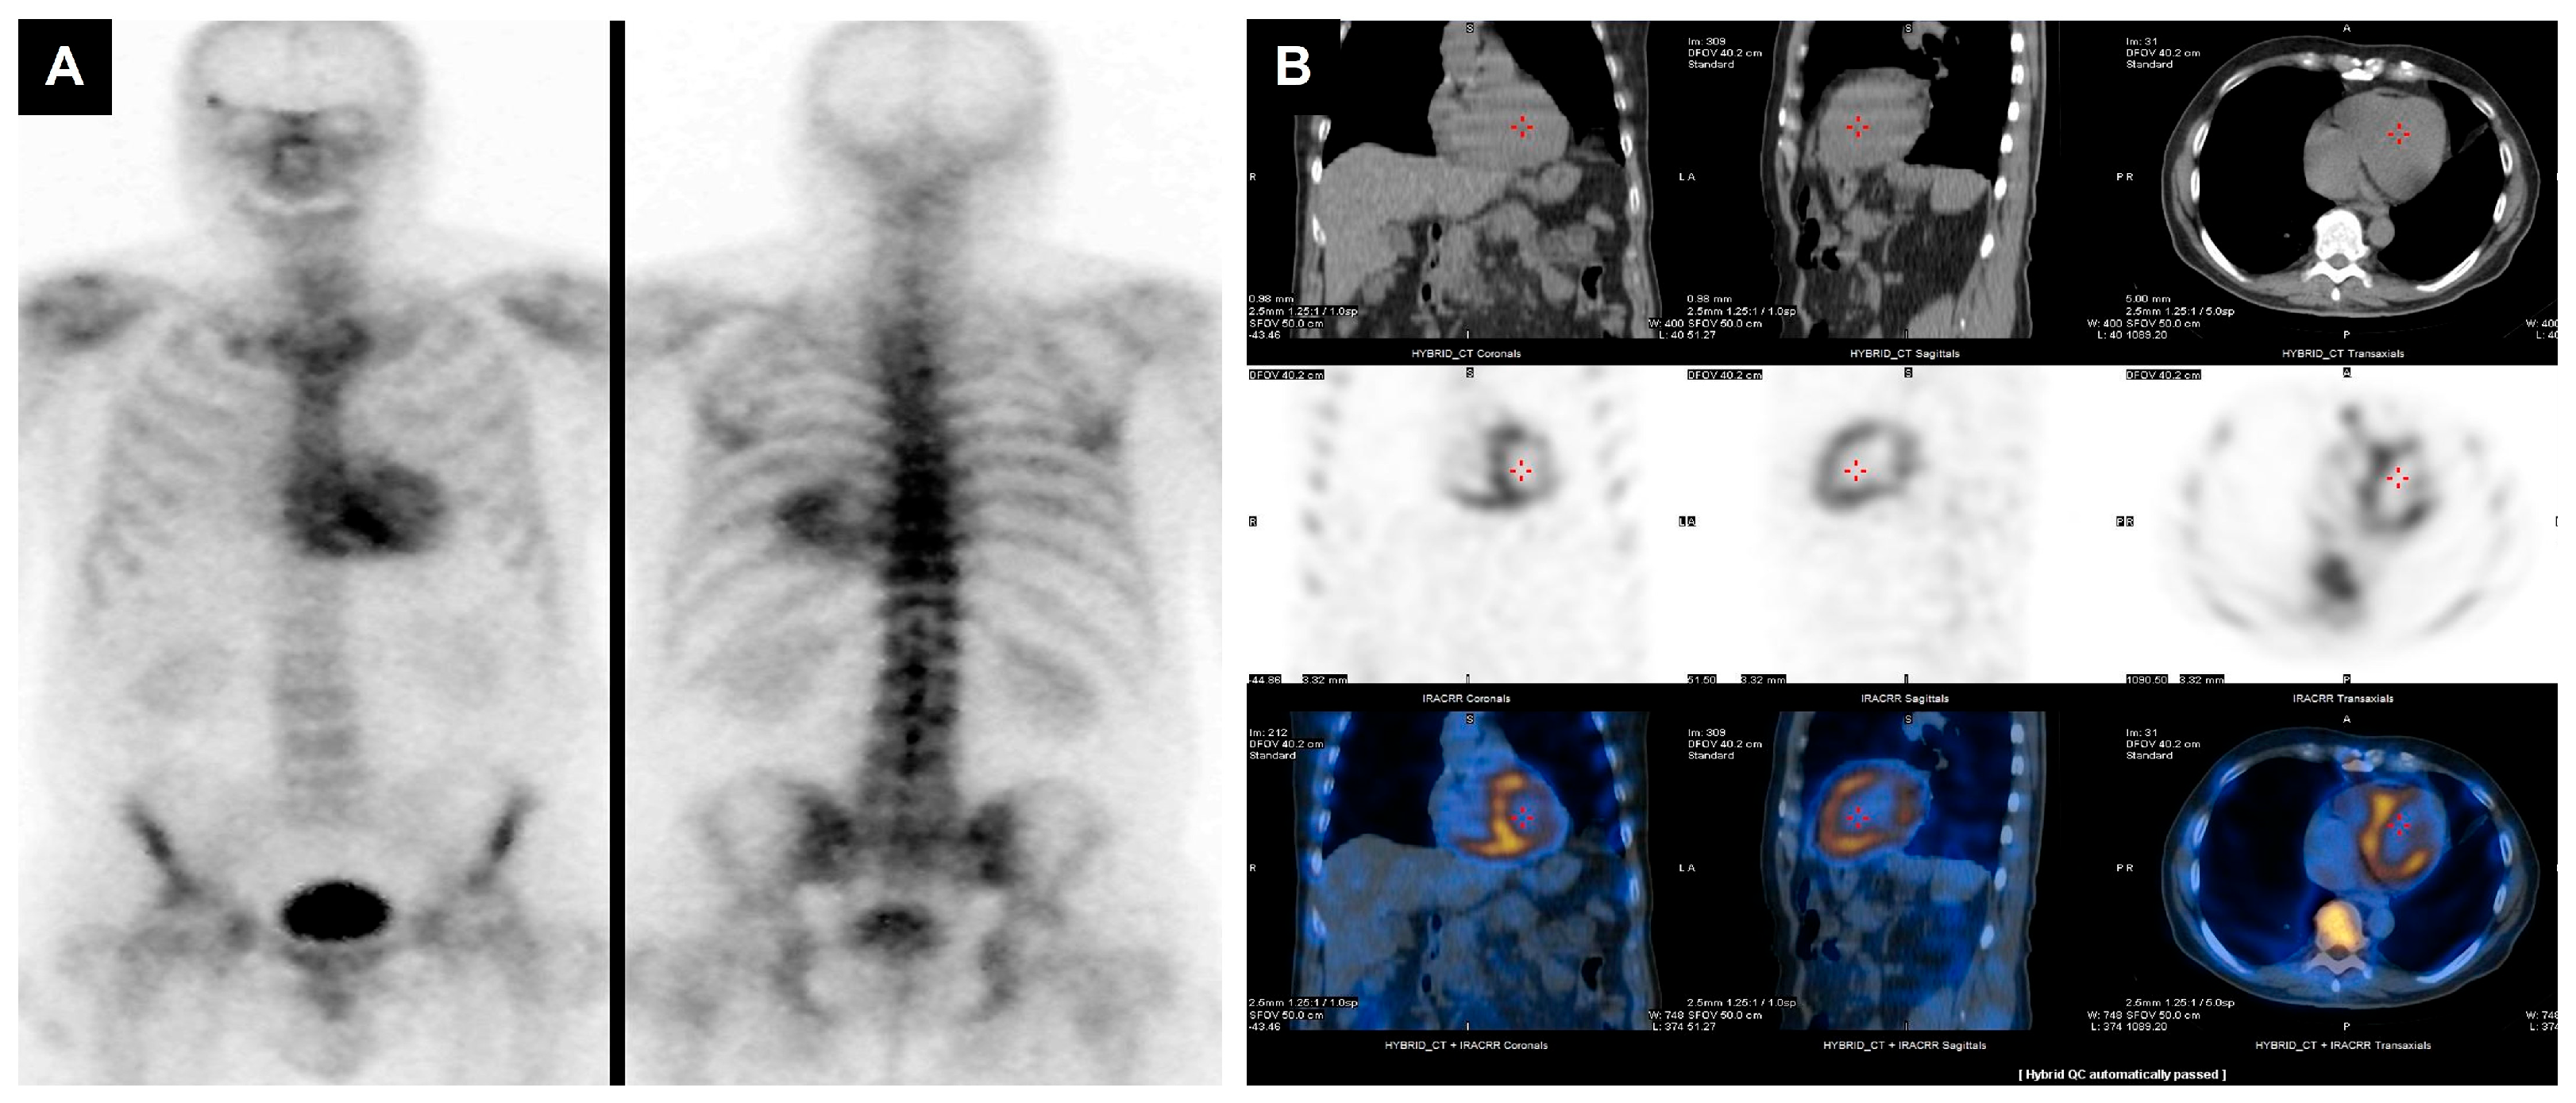

- Osiecki, S.; Sterliński, M.; Marciniak-Emmons, M.; Dziuk, M. Feasibility of 18FDG PET in the Cardiac Inflammation. Int. J. Cardiovasc. Imaging 2021, 37, 1097–1104. [Google Scholar] [CrossRef]

- Sarocchi, M.; Bauckneht, M.; Arboscello, E.; Capitanio, S.; Marini, C.; Morbelli, S.; Miglino, M.; Congiu, A.G.; Ghigliotti, G.; Balbi, M.; et al. An Increase in Myocardial 18-Fluorodeoxyglucose Uptake Is Associated with Left Ventricular Ejection Fraction Decline in Hodgkin Lymphoma Patients Treated with Anthracycline. J. Transl. Med. 2018, 16, 295. [Google Scholar] [CrossRef]

- Boughdad, S.; Latifyan, S.; Fenwick, C.; Bouchaab, H.; Suffiotti, M.; Moslehi, J.J.; Salem, J.-E.; Schaefer, N.; Nicod-Lalonde, M.; Costes, J.; et al. 68 Ga-DOTATOC PET/CT to Detect Immune Checkpoint Inhibitor-Related Myocarditis. J. Immunother. Cancer 2021, 9, e003594. [Google Scholar] [CrossRef] [PubMed]